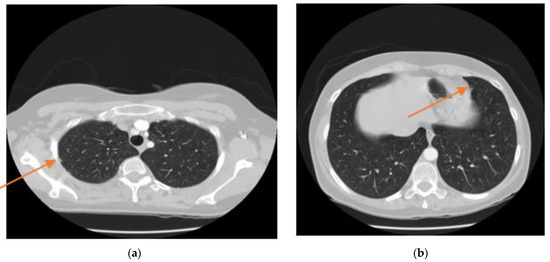

- Image binarization: In this process, a binary image is created with two values on the grey surface, i.e., black and white. The lung region poses a black colour with the value zero. Figure 8 shows the binarization process of a CT image.